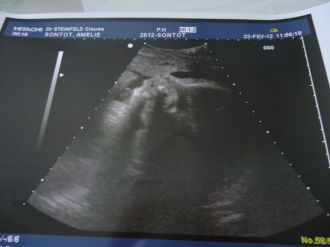

Et voila j'ai eu ma dernière echo hier a 11 h , c'est la dernière fois qu on le vois avant qu'il soit dans nos bras :)

il pesé 2kilos 147 le gynéco l'estime a terme a 3kilos200! un beau bébé :) a eu le droit a un petit cliché du profil de mon fils je vous met la photo xd